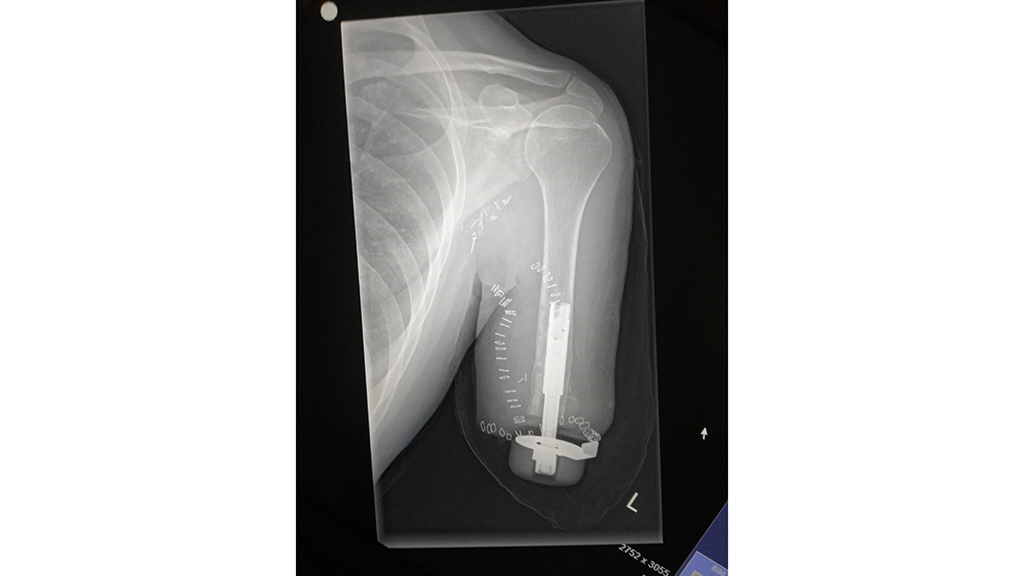

Nach einiger Zeit mit konventionellem Schaftsystem wurde im November 2019 die transhumerale Osseointegration mit selektivem Nerventransfer durchgeführt (Abb. 1). Die Osseointegration erfolgte mit einem Implantat des schwedischen Herstellers Integrum. Bei der TMR-Operation konnten 5 Hotspots zur gezielten Ansteuerung der myoelektrischen Komponenten gebildet werden.